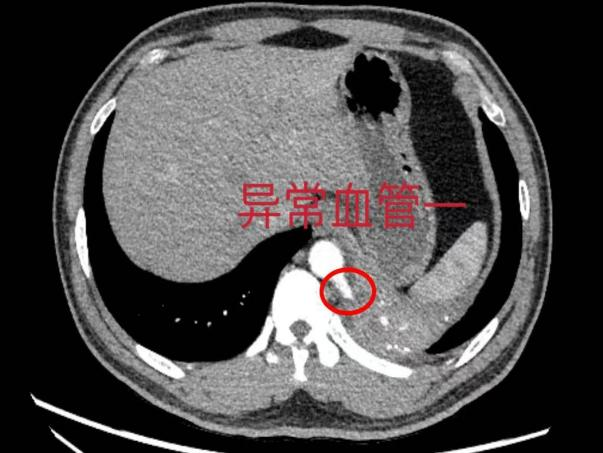

医院心胸外科主任谈磊解释道:肺隔离症好比患者多长出来一叶肺,医学上一般称这多出来的肺组织为“隔离肺”。该组织有自己的循环系统,通常由人体最粗大的主动脉发出异常分支供血,这支血管如果出现破裂,将导致肺部出现大出血,后果不堪设想。经过仔细阅片,谈磊主任发现李先生增强CT显示有2支粗大的异常血管,更为罕见。